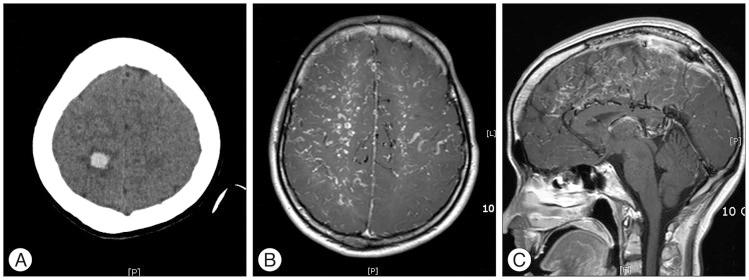

We are reporting an unusual case of dural arteriovenous fistula (AVF) of the superior sagittal sinus (SSS) after tamoxifen treatment for breast cancer. A 30-year-old female arrived at the emergency room with a sudden headache and left sided weakness and sensory loss. In her past medical history, she was diagnosed with breast cancer 1 year prior, and subsequently underwent a breast conserving mastectomy with whole breast radiation and adjuvant chemotherapy with tamoxifen. At the time of admission, computed tomography showed a small acute intracerebral hemorrhage at the right parietal cortex, and magnetic resonance imaging showed that a dural AVF at the SSS with a prominent and tortuous venous enhancement along the centrum semiovale was present. Cerebral angiography showed that the dural AVF at the mid-portion of the SSS with meningeal arterial feeding vessels entering the wall of the SSS, then draining through the dilated cortical veins. Our patient had no signs of active malignancy or any abnormalities in her coagulation profile, so it can be concluded that the tamoxifen was the likely cause of the SSS thrombosis and dural AVF. The dural AVF was treated by an endovascular coil embolization for the arterialized segment of the SSS. The patient dramatically recovered favorably from left side motor and sensory deficit. The best clinical approach is to screen potential patients of tamoxifen hormonal therapy and educate them on the sign and symptoms of life threatening thromboembolic events while taking tamoxifen.

我们报告了一例在他莫昔芬治疗乳腺癌后发生上矢状窦(SSS)硬脑膜动静脉瘘(AVF)的罕见病例。一名30岁女性因突发头痛、左侧肢体无力和感觉丧失入住急诊室。既往病史显示,她1年前被诊断为乳腺癌,随后接受了保乳乳房切除术、全乳放疗以及他莫昔芬辅助化疗。入院时,计算机断层扫描显示右侧顶叶皮质有一小片急性脑内出血,磁共振成像显示SSS处存在硬脑膜AVF,沿半卵圆中心有明显且迂曲的静脉强化。脑血管造影显示SSS中部的硬脑膜AVF,有脑膜动脉供血血管进入SSS壁,然后通过扩张的皮质静脉引流。我们的患者没有活动性恶性肿瘤迹象,凝血指标也无任何异常,因此可以得出结论,他莫昔芬可能是导致SSS血栓形成和硬脑膜AVF的原因。通过血管内弹簧圈栓塞术治疗了SSS动脉化段的硬脑膜AVF。患者左侧运动和感觉功能障碍显著好转。最佳临床处理方法是筛查他莫昔芬激素治疗的潜在患者,并告知他们在服用他莫昔芬期间危及生命的血栓栓塞事件的体征和症状。